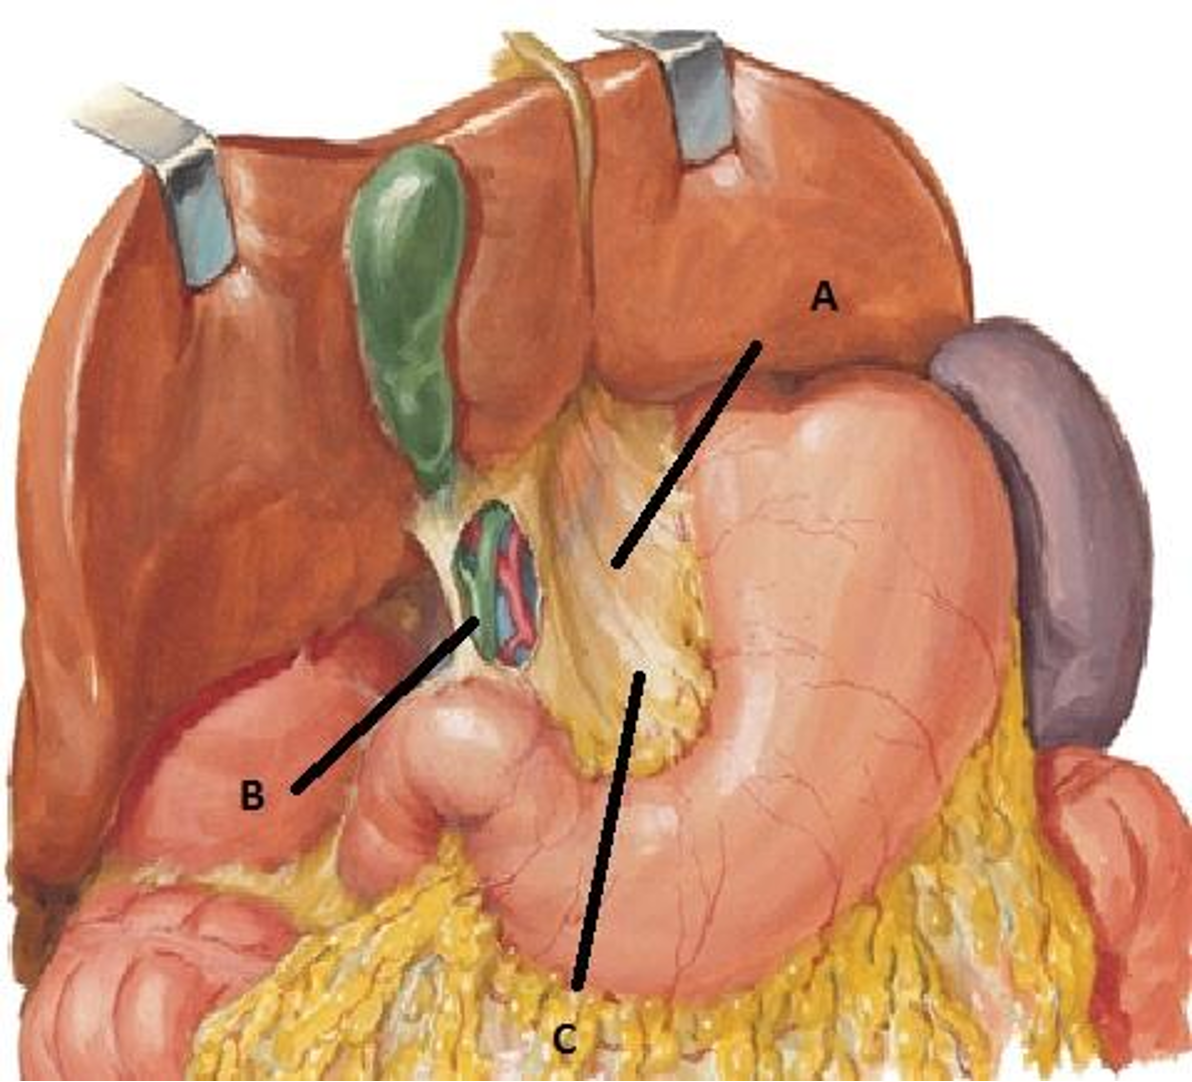

Principles of surgical management:

- control of bleeding,

- removal of devitalized tissue, and

- adequate drainage.

-

Bleeding vessels & biliary radicles are individually ligated.

-

Pringle’s maneuver: clamping the hepatoduodenal ligament (the free border of the lesser omentum)

-

Perihepatic packing- if fail to control bleeding.

-

Packs removed in 48 hours.